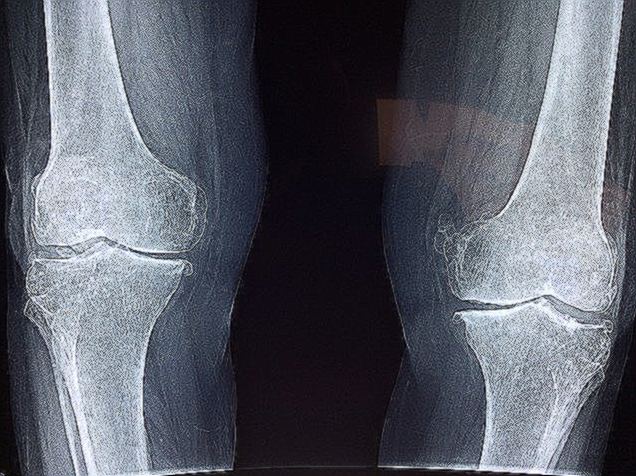

무릎 물빼기 시술에 대해 알아보기 전에 왜 무릎에 물이 차는지 알아보도록 하겠습니다. 사실 무릎은 원래 물이 차 있는 조직입니다. 무슨 말인지 잘 모르시겠다고요? 잘 따라와 보시기 바랍니다. 무릎을 비롯한 관절에는 연골만 있는 것으로 생각하는 분들이 많으십니다. 하지만 이 연골도 관절액이라는 액체에 의해 보호되고 있습니다. 관절 내에 액체가 들어있기 때문에 체중의 몇 배에 달하는 하중도 버틸 수 있는 것 입니다.

하지만 노화로 인해 관절염이나 기타 관절질환 등이 발생한다면 이 관절액이 과도하게 생성될 수 있습니다. 그럼 관절 내부가 과도한 압력을 받게 됩니다. 이로 인해 무릎 관절이 뻐근한 증상과 함께 통증이 느껴집니다. 직접적인 원인이 무릎 관절액의 과다이기 때문에 무릎 물빼기를 진행하시면 효과를 경험하실 수 있습니다.

그렇다면 언제 무릎 물빼기를 시행해야할까요? 앞서 말씀드린 것 처럼 무릎 관절 내에 액체가 존재하는 것은 지극히 정상입니다. 따라서 일반적으로 봤을 때 무릎 물빼기 시술을 받으실 필요는 없습니다. 하지만 관절액의 양이 위에서 언급한 모종의 사유로 너무 많아질 경우 압력이 많이 상승할 수 있습니다. 이 경우 무릎연골에 제대로 된 영양분 공급이 어려울 수 있어 무릎 관절의 약화를 초래할 수 있습니다.

이러한 경우에는 번거롭더라도 무릎에 물이 찰때마다 무릎 물빼기 시술을 시행해야 할 수 있습니다. 하지만 무릎 물빼기 시점에 대해서는 치료에 임하는 의사마다 다소 다른 기준을 가지고 있습니다. 무릎 통증이 심하고 붓기와 열감이 있는 경우에는 자주 빼주는 것이 유리한 것으로 알려져 있습니다. 혹은 스테로이드제 처방 등을 통해 무릎 관절의 관절액은 줄여주는 방법도 적용될 수 있습니다. 통증 경감을 위한 진통제와 소염제도 도움이 되지요.